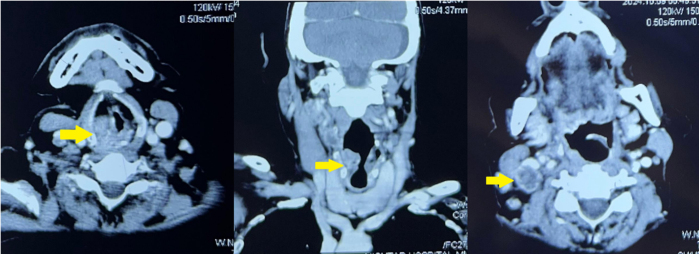

Case presentation: A 68-year-old Pakistani male with a prior diagnosis of LSCC presented with new-onset generalized tonic-clonic seizures. He had previously undergone total laryngectomy, radiotherapy, and chemotherapy. Brain MRI revealed a right frontal lobe lesion with surrounding edema, consistent with a solitary metastasis. Histopathology following craniotomy confirmed metastatic squamous cell carcinoma. The patient was managed with antiepileptics and referred for palliative whole-brain radiotherapy. He and his family opted for palliative care, declining further aggressive treatment.